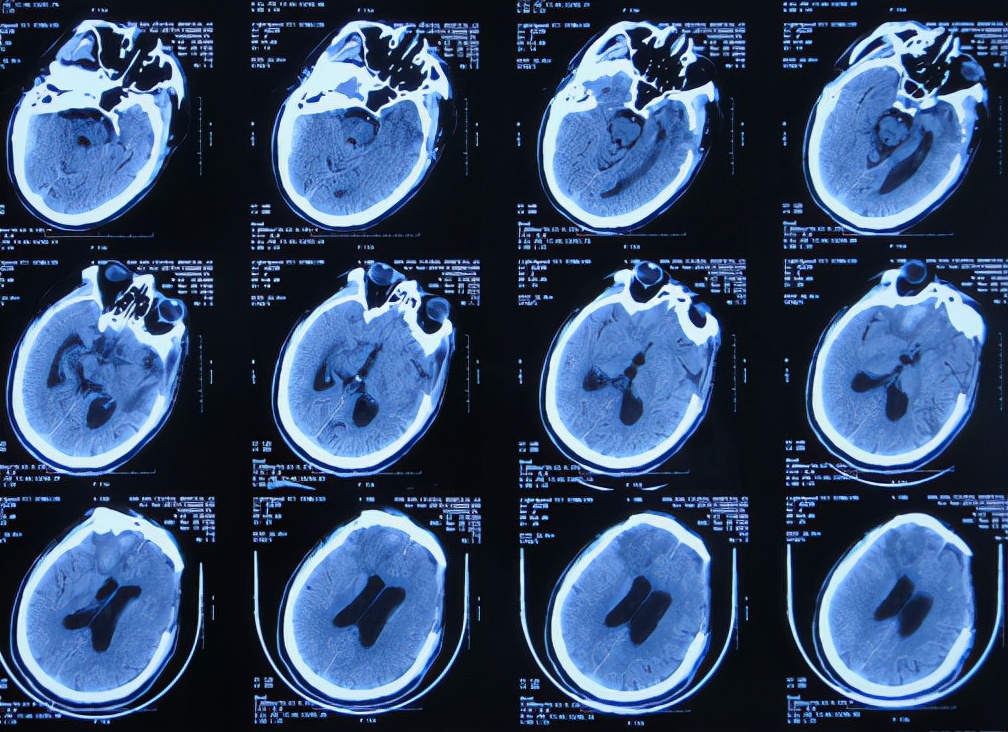

2019年10月20日患者骑电动车在马路上行驶时被大货车撞倒,当时意识清楚,只感到有些头晕,未在意就自行回家,但回家后约3-4小时出现头晕加重,并伴有恶心呕吐的症状,家人急送到当地的河北省邯郸市某医院,查头颅CT示脑出血( 图-1 );既往病史2015年曾因头部外伤致硬膜下血肿,进行了钻孔引流术。

图-1: 2019年10月20日头颅CT

急诊进行了开颅去骨瓣血肿清除术,术后次日查头颅CT示去骨瓣术后( 图-2 )。

图-2: 2019年10月21日头颅CT

开颅术后第2天即2019年10月22日,仍昏迷,查头颅CT示积血未见减少( 图-3 ),给予腰椎穿刺术。

图-3: 2019年10月22日头颅CT

开颅术后第4天即2019年10月24日,查头颅CT示积血仍未明显减少( 图-4 )。

图-4: 2019年10月24日头颅CT